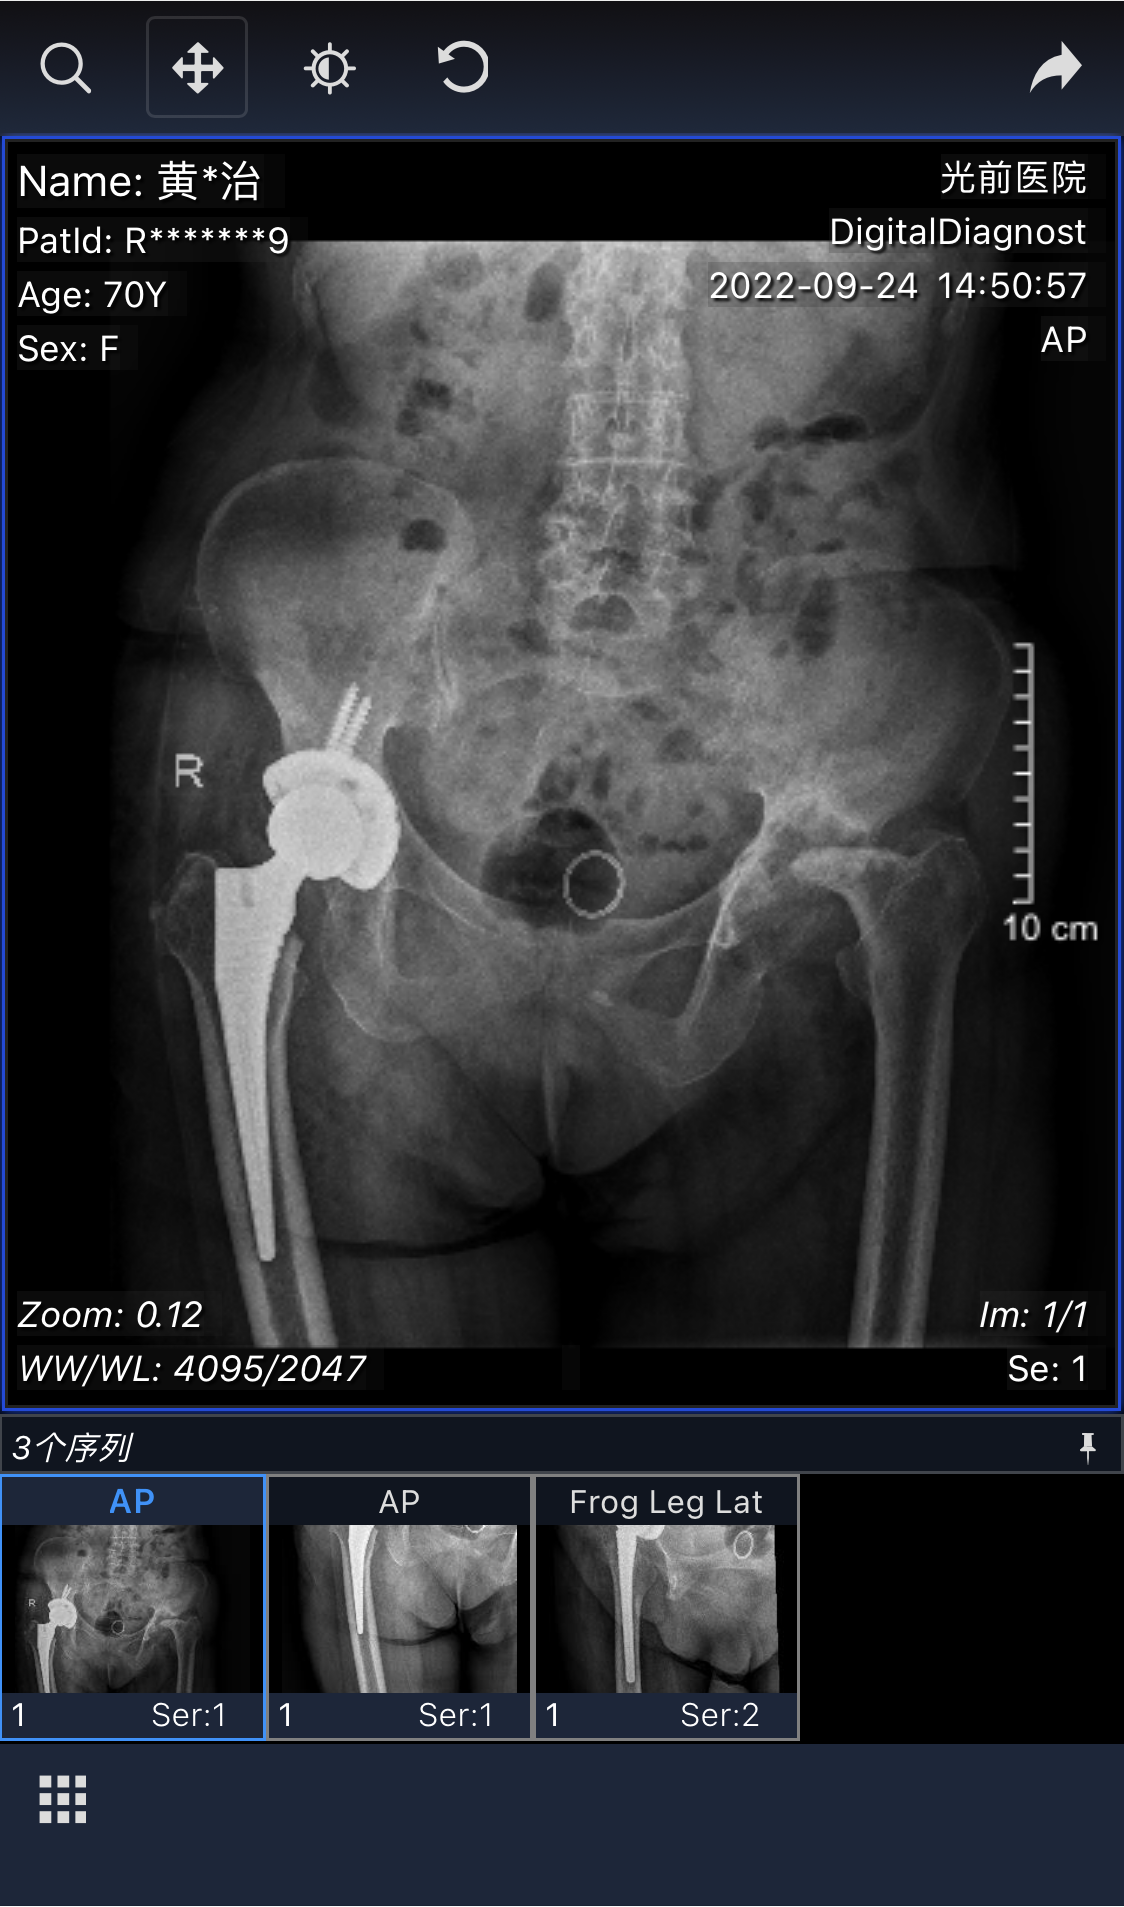

2022年9月20日,黃主任為黃阿婆行右側(cè)人工全髖關(guān)節(jié)置換,手術(shù)很成功。術(shù)后第二天,黃阿婆就能扶著拐杖慢慢下地,1周后便可在病房扶著拐杖緩慢行走。黃阿婆及家屬非常滿意,陳阿公(黃阿婆丈夫)有感而發(fā),送來一首詩(shī),表達(dá)感激之情。

(? 2022.9.20?)

手術(shù)前后對(duì)比